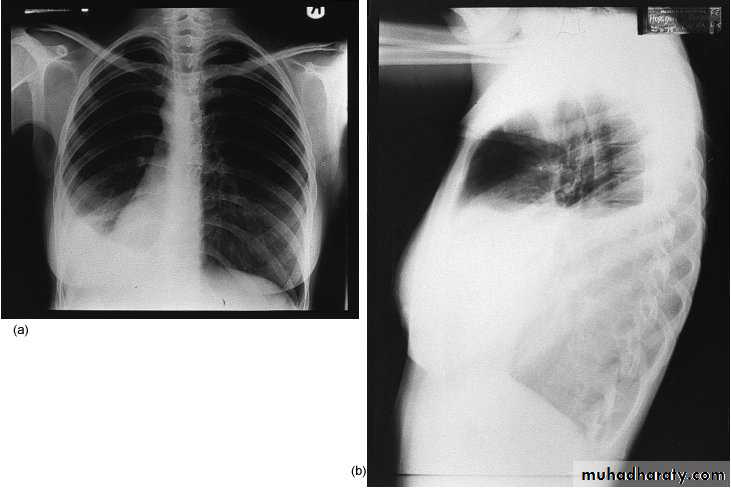

Thoracic incisions

1-Thoracostomy(chest tube )

In pnemothorax at 5nd ICS ant. axillary line

2-Mediastenial vertical incision used for cardiac op

3-Intercostals at 5th ICS & 8th ICS

4-Thoracoabdominal extended to Rt or Lt paramedian used for oesophagial op